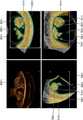

도 1은 일부 실시예에 따른, 초음파 진단 장치(1000)가 3 차원 초음파 영상이 나타내는 디스플레이 볼륨의 표면의 위치를 2 차원 초음파 영상에 나타내는 예시를 도시한 도면이다.1 is a diagram illustrating an example in which a position of a surface of a display volume represented by a 3D ultrasound image is shown on a 2D ultrasound image by the ultrasound

도 1을 참조하면, 초음파 진단 장치(1000)는, 대상체의 3 차원 초음파 영상(50)이 나타내는 디스플레이 볼륨의 표면의 위치를 2 차원 초음파 영상(40)에 나타낼 수 있다.1, the ultrasonic

도 1(a)를 참조하면, 초음파 진단 장치(1000)는 환자의 담낭을 나타내는 2 차원 초음파 영상(40)을 디스플레이할 수 있다. 초음파 진단 장치(1000)는 2 차원 초음파 영상(40) 상에, 3 차원 초음파 영상(50)으로 디스플레이하고자 하는 관심 영역(110)을 설정하는 사용자 입력을 수신할 수 있다. 예를 들어, 초음파 진단 장치(1000)는 3 차원 렌더링이 시작될 지점들(110)을 선택하는 사용자 입력을 수신할 수 있다. 또한, 초음파 진단 장치(1000)는 3 차원 영상으로 표현할 볼륨의 깊이(115)를 선택하는 사용자 입력을 수신할 수 있다. 선택된 지점들(110)과 선택된 깊이(115)에 의해 정의되는 영역(110, 115)은 관심 영역(110, 115)으로 언급될 수 있다.Referring to FIG. 1 (a), the ultrasound

도 1(b)를 참조하면, 관심 영역(110, 115)을 설정하는 사용자 입력을 수신함에 따라, 초음파 진단 장치(1000)는 설정된 관심 영역(110, 115)에 대한 3 차원 초음파 영상(50)을 디스플레이할 수 있다.Referring to FIG. 1B, the ultrasound

이 때, 초음파 진단 장치(1000)는, 대상체의 3 차원 초음파 영상(50)이 나타내는 디스플레이 볼륨의 표면의 위치를 2 차원 초음파 영상(40)에 나타낼 수 있다.At this time, the ultrasonic

도 1(a)에 도시된 바와 같이, 환자의 담낭 내에는 침전물이 쌓여있을 수 있으며, 사용자는 침전물의 모양, 크기 또는 형태를 관찰하기 위해, 침전물이 포함된 관심 영역(110, 115)을 3 차원 초음파 영상(50)으로 디스플레이할 수 있다. 이 경우, 침전물 위에 노이즈 물체(125)가 존재할 수 있다. 침전물 위에 노이즈 물체(125)가 존재하는 경우, 3 차원 초음파 영상(50)이 나타내는 디스플레이 볼륨의 표면은 침전물이 아닌 노이즈 물체(125)일 수 있다. 노이즈 물체(125)는 도 1에 도시된 바와 같이, 2 차원 초음파 영상(40)에서는 침전물 또는 담낭 조직과 구별 가능하지만, 3 차원 초음파 영상(50)에서는 침전물 또는 담낭 조직과 구별하기 어려울 수 있다.As shown in FIG. 1 (a), the gallbladder of the patient may have accumulated deposits, and the user may insert the region of

초음파 진단 장치(1000)는 노이즈 물체(125)를 제거하는 사용자 입력을 수신할 수 있다.The ultrasonic

예를 들어, 초음파 진단 장치(1000)는 볼륨 렌더링 시 3 차원 초음파 영상(50)으로 렌더링하지 않을 영역을 삭제하는 사용자 입력을 수신할 수 있다. 구체적으로, 초음파 진단 장치(1000)는 3 차원 초음파 영상(50) 내의 노이즈 물체(125)를 깎아내는 사용자 입력을 수신할 수 있다. 노이즈 물체(125)를 깎아내는 사용자 입력을 수신함에 따라, 초음파 진단 장치(1000)는 노이즈 물체(125)에 대응하는 복셀의 불투명도를 0으로 설정할 수 있다.For example, the ultrasound

노이즈 물체(125)에 대응하는 복셀의 불투명도를 0으로 설정함에 따라, 초음파 진단 장치(1000)는 노이즈 물체(125)를 3 차원 초음파 영상(50)으로 렌더링하지 않을 수 있다. 이에 따라, 초음파 진단 장치(1000)는 침전물을 디스플레이 볼륨의 표면으로 나타내는 3 차원 초음파 영상(50)을 디스플레이할 수 있다.The ultrasound

그러나, 이 경우에도, 디스플레이 볼륨의 표면을 깎아낼 때, 3 차원 초음파 영상(50)에서는 노이즈 물체(125)를 침전물 또는 담낭 조직과 구별하기 어렵기 때문에, 사용자는 3 차원 초음파 영상(50)만을 보고 깎여진 깊이가 자신이 원하는 깊이인지, 즉, 노이즈 물체(125)가 제거 되었는지를 알기 어렵다.In this case, however, it is difficult to distinguish the

초음파 진단 장치(1000)는 대상체의 3 차원 초음파 영상(50)이 나타내는 디스플레이 볼륨의 표면의 위치를 2 차원 초음파 영상(40)에 나타낼 수 있다. 2 차원 초음파 영상(40)에서는 노이즈 물체(125)가 침전물 또는 담낭 조직과 구별 가능하므로, 디스플레이 볼륨의 표면의 위치를 2 차원 초음파 영상(40)에 나타냄으로써, 사용자는 깎여진 깊이가 자신이 원하는 깊이인지를 알 수 있다.The ultrasound

예를 들어, 도 1(a)를 다시 참조하면, 초음파 진단 장치(1000)는 2 차원 초음파 영상(40) 상에 3 차원 초음파 영상(50)이 나타내는 디스플레이 볼륨의 표면의 위치를 라인(120)으로 나타낼 수 있다.For example, referring again to FIG. 1 (a), the ultrasound

3 차원 초음파 영상(50)에서, 사용자의 입력에 의해 디스플레이 볼륨의 표면이 깎여짐에 따라, 초음파 진단 장치(1000)는 디스플레이된 라인(120) 중 깎여진 영역에 대응되는 지점들을, 깎여진 깊이만큼 아래로 내림으로써, 디스플레이 볼륨의 표면의 위치를 나타낼 수 있다. 예를 들어, 디스플레이 볼륨이 노이즈 물체(125)를 포함하는 경우, 초음파 진단 장치(1000)는 디스플레이 볼륨의 표면의 위치를 나타내는 라인(120)이 노이즈 물체(125) 위에 지나도록, 2 차원 초음파 영상(40) 상에 라인(120)을 디스플레이할 수 있다. 또한, 사용자의 입력에 의해 노이즈 물체(125)의 3 차원 데이터가 3 차원 렌더링 시 제외됨에 따라, 초음파 진단 장치(1000)는 볼륨의 표면의 위치를 나타내는 라인(120)이 노이즈 물체(125) 아래를 지나도록 2 차원 초음파 영상(40) 상에 라인(120)을 디스플레이할 수 있다.In the

또한, 초음파 진단 장치(1000)는, 3 차원 초음파 영상(50) 상에, 2 차원 초음파 영상(40)이 나타내는 대상체의 단면의 위치를 나타내는 라인(130)을 디스플레이할 수 있다. 이에 따라, 사용자는, 2 차원 초음파 영상(40)이 나타내는 단면에 대응되는 3 차원 초음파 영상(50) 상의 위치를 확인할 수 있다.